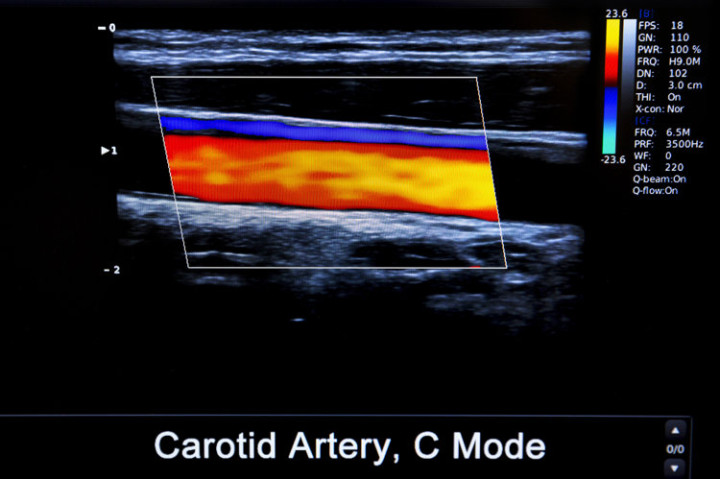

血栓栓塞是由于动/静脉内形成了血凝块导致的潜在性致死性疾病。血栓会在血管内随着血液循环不断游离,在任何年龄、任意时间都可能发生,一旦堵塞血管,会导致全身的血液循环系统瘫痪,导致细胞死亡,威胁全身健康。

血栓根据发生部位的不同以及表现可分为心脏血栓、静脉血栓和动脉血栓,不同血栓容易堵塞的部位不同。